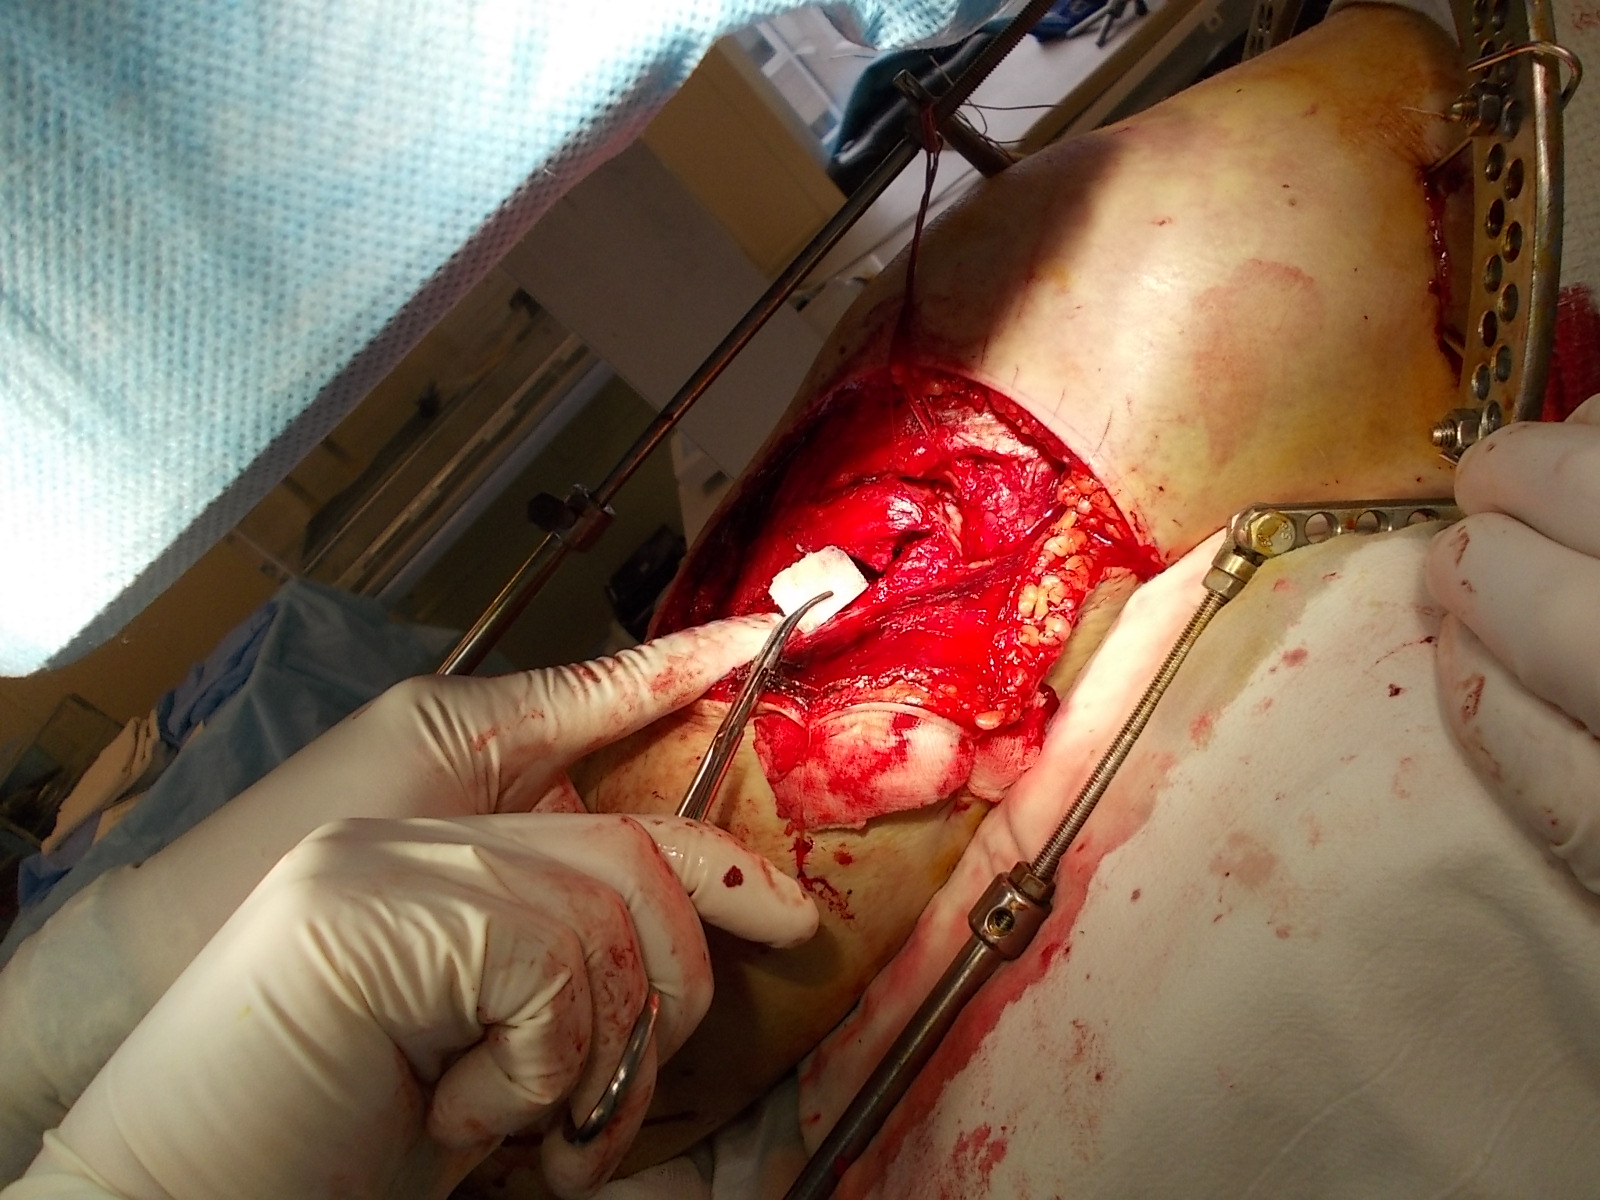

Использование материала Остеоматрикс при импрессионном оскольчатом переломе наружного мыщелка большеберцовой кости по типу Schatzker II.

Операция - открытая репозиция, остеосинтез большеберцовой кости опорной пластиной с костной ксенопластикой маетриалом "Остеоматрикс". На контрольных снимках в три и шесть месяцев имеется консолидация перелома, миграции фиксатора нет, имеется остеоинтеграция ксенопластического материала. Функция коленного сустава полная.